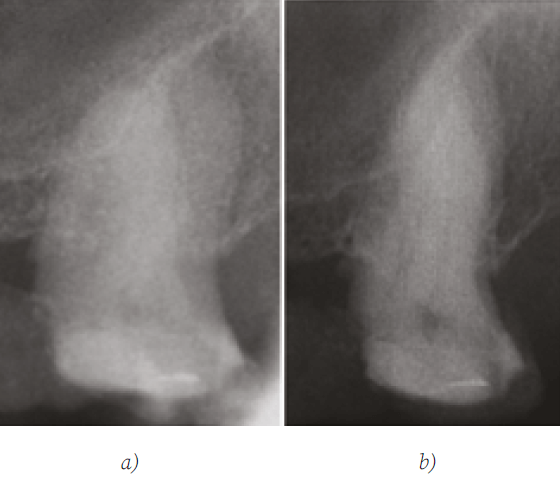

A la evaluación clínica, a la prueba de sensibilidad al frío realizada con cloruro de etilo (Hygenic Endo Ice, Coltene/Whaledent Inc., OH, USA) dio resultado positivo, negativo a la prueba de sensibilidad al calor, negativo a las pruebas de percusión vertical, horizontal y a la palpación sobre apical, sin presencia de tumefacción ni trayecto fistuloso. Se diagnosticó en el segundo molar superior izquierdo (27) pulpitis irreversible sintomática con tejidos periapicales normales 23. Se realizó el registro radiográfico con Rx periapical ortoradial y distoradial, como indica Cantatore et al. 2 y Acosta et al. 24, para evaluar la presencia y número de raíces y conductos. Dicha evaluación radiográfica indico falta de definición de conducto en raíz MV compatible con calcificación del SCR, ninguna variación de la anatomía de la raíz fue detectada. Figura 1.

Figura 1. Rx inicial orto (a) y distorradial (b)